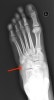

X-ray에서는 종입방관절면을 따라 골절선을 볼 수 있습니다.

초기의 X-ray에서는 발견할 수 없어도 골위축증이 시작되는 3주일 후의 X-ray에서 발견되는 경우가 있습니다.

X-ray : 입방골 압박골절(Cuboid fracture, Nutcracker fracture)